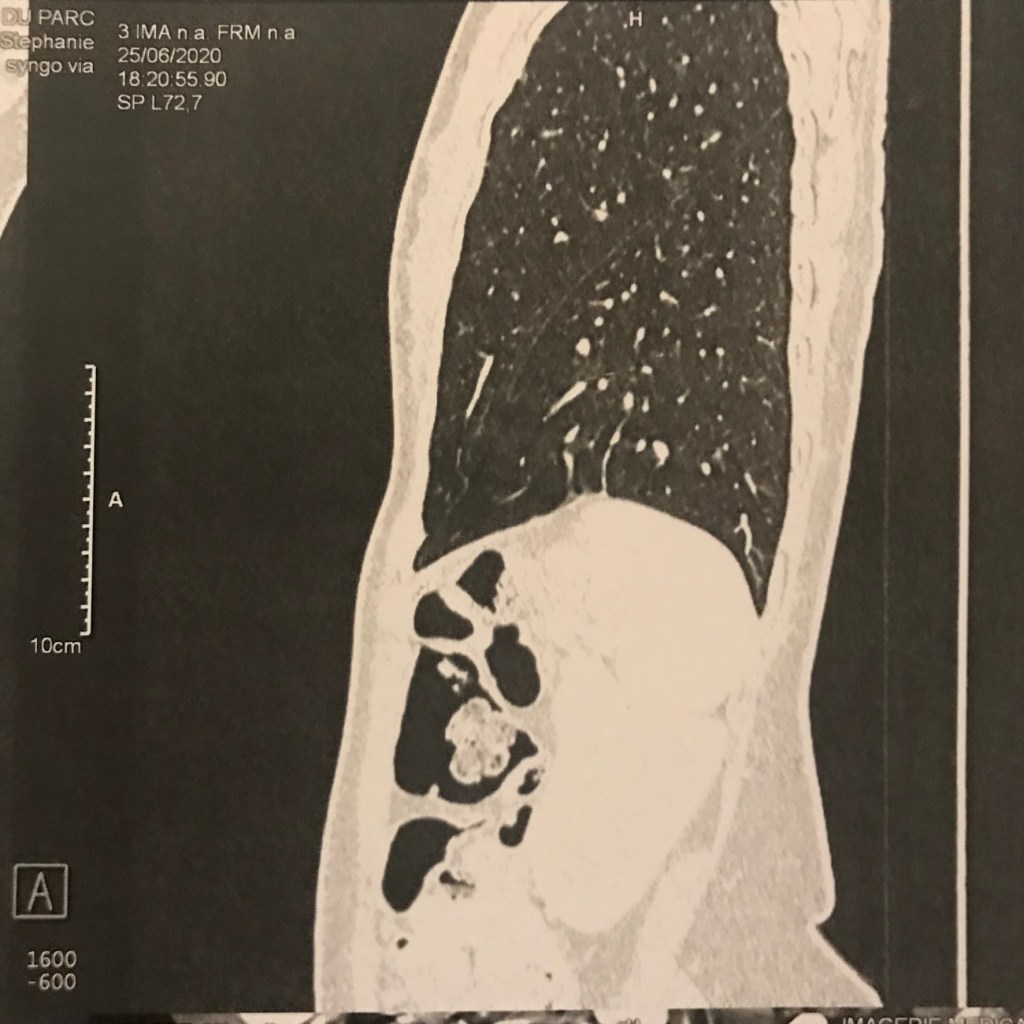

- La radiologue : « Vous êtes essoufflée, Madame? »

- Moi: « Pardon, non, je cours tout le temps, ça va bien ! Mais pourquoi ? »

- La radiologue : « La bonne nouvelle, ce que ce n’est pas un cancer. Par contre, votre scanner montre que vous avez une sarcoïdose pulmonaire: une maladie rare qui touche les jeunes dont la cause est inconnue avec l’accumulation de granulomes dans les organes»

- Mon médecin traitant le lendemain: « Mme P., il faut qu’on se voit ! Il faut faire des examens complémentaires, voir le pneumologue, l’ophtalmo, le cardiologue, faire une épreuve d’effort, peut-être prendre des corticoïdes…Vous avez des sueurs nocturnes ?».

- Moi, surprise : « Euh non. Mais oui, d’accord, à ce soir alors ! ».

Quand elle raccroche, je réalise que c’est la première fois en 10 ans qu’elle m’appelle. Je regarde enfin le compte-rendu de scanner : « Stade II » et les clichés. Oups, je n’ai pas de symptômes certes mais mon ganglion à l’aine droit et le scanner de mes poumons montrent bien que mon corps se défend !

Je cours quand même et je cherche à savoir si je ressens un truc qui cloche. Rien du tout, je suis en pleine forme et je savoure le fait d’être en vie.

[…] il faut aussi que je me soigne, pour l’instant j’ignore comment va évoluer ma sarcoïdose. J’ai l’impression que le fait d’être sportive contribuer à mon état […]

[…] répondu que non. Je préparais mon premier marathon et ça ne me gênait pas du tout. J’étais tombée des nues quand elle m’avait montrée mon scanner avec l’état de … Elle m’avait aussi dit: “La bonne nouvelle, c’est que ce n’est pas un […]